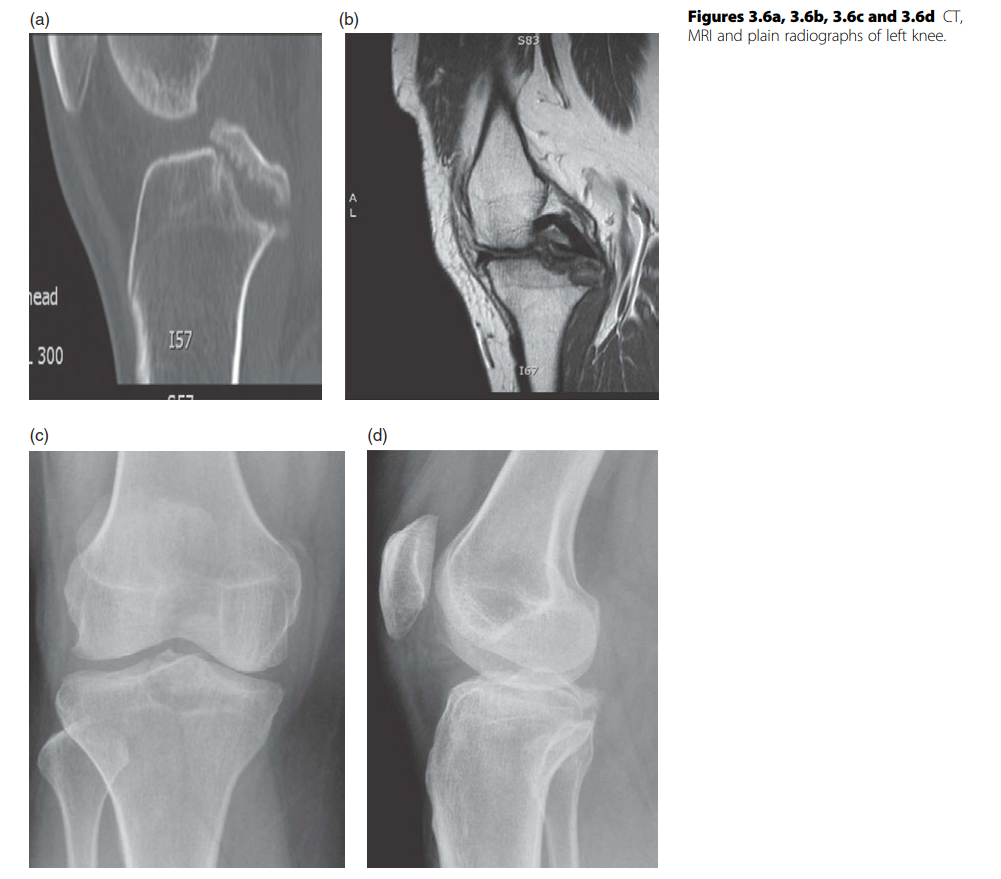

KNEE Structured oralexamination question4: Unicondylar knee arthroplasty ( UKA ) versus high tibial osteotomy…

KNEE Structured oralexamination question5: Unicondylar knee arthroplasty (UKA) versus total knee replacement …